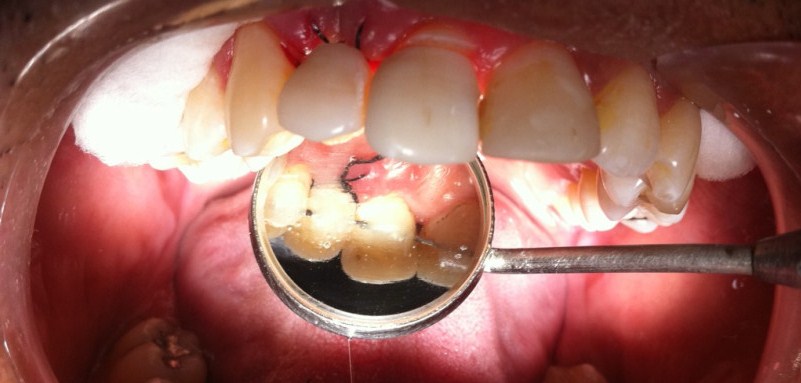

Futebol é um esporte muito perigoso, ainda mais pra atletas de fim de semana. Esse meu paciente tomou uma cotoveladas DAQUELAS na boca, resultando em duas fraturas dentárias…

Não bati nenhuma foto dele na segunda, porque fui pega de surpresa e também não sabia muito o que fazer na hora… realizei a exodontia do dente 12 e o 11 deixei a raiz, pois queria a opinião de um endodontista.

Não poderia pedir pra ele voltar em um outro dia, então pensei em utilizar os próprios dentes do paciente como provisórios. Desgastei as laterais e a parte cervical para encaixar melhor.